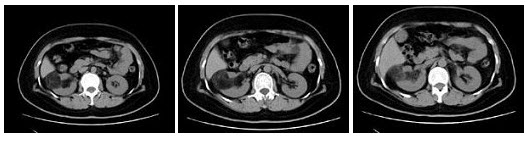

248、多项选择题 肾透明细胞癌CT增强扫描的强化特点是()

A.延迟期强化常不及肾实质

B.可为不规则边缘强化

C.可为不均匀斑片状强化

D.少数可无明显对比增强

E.动脉期强化明显